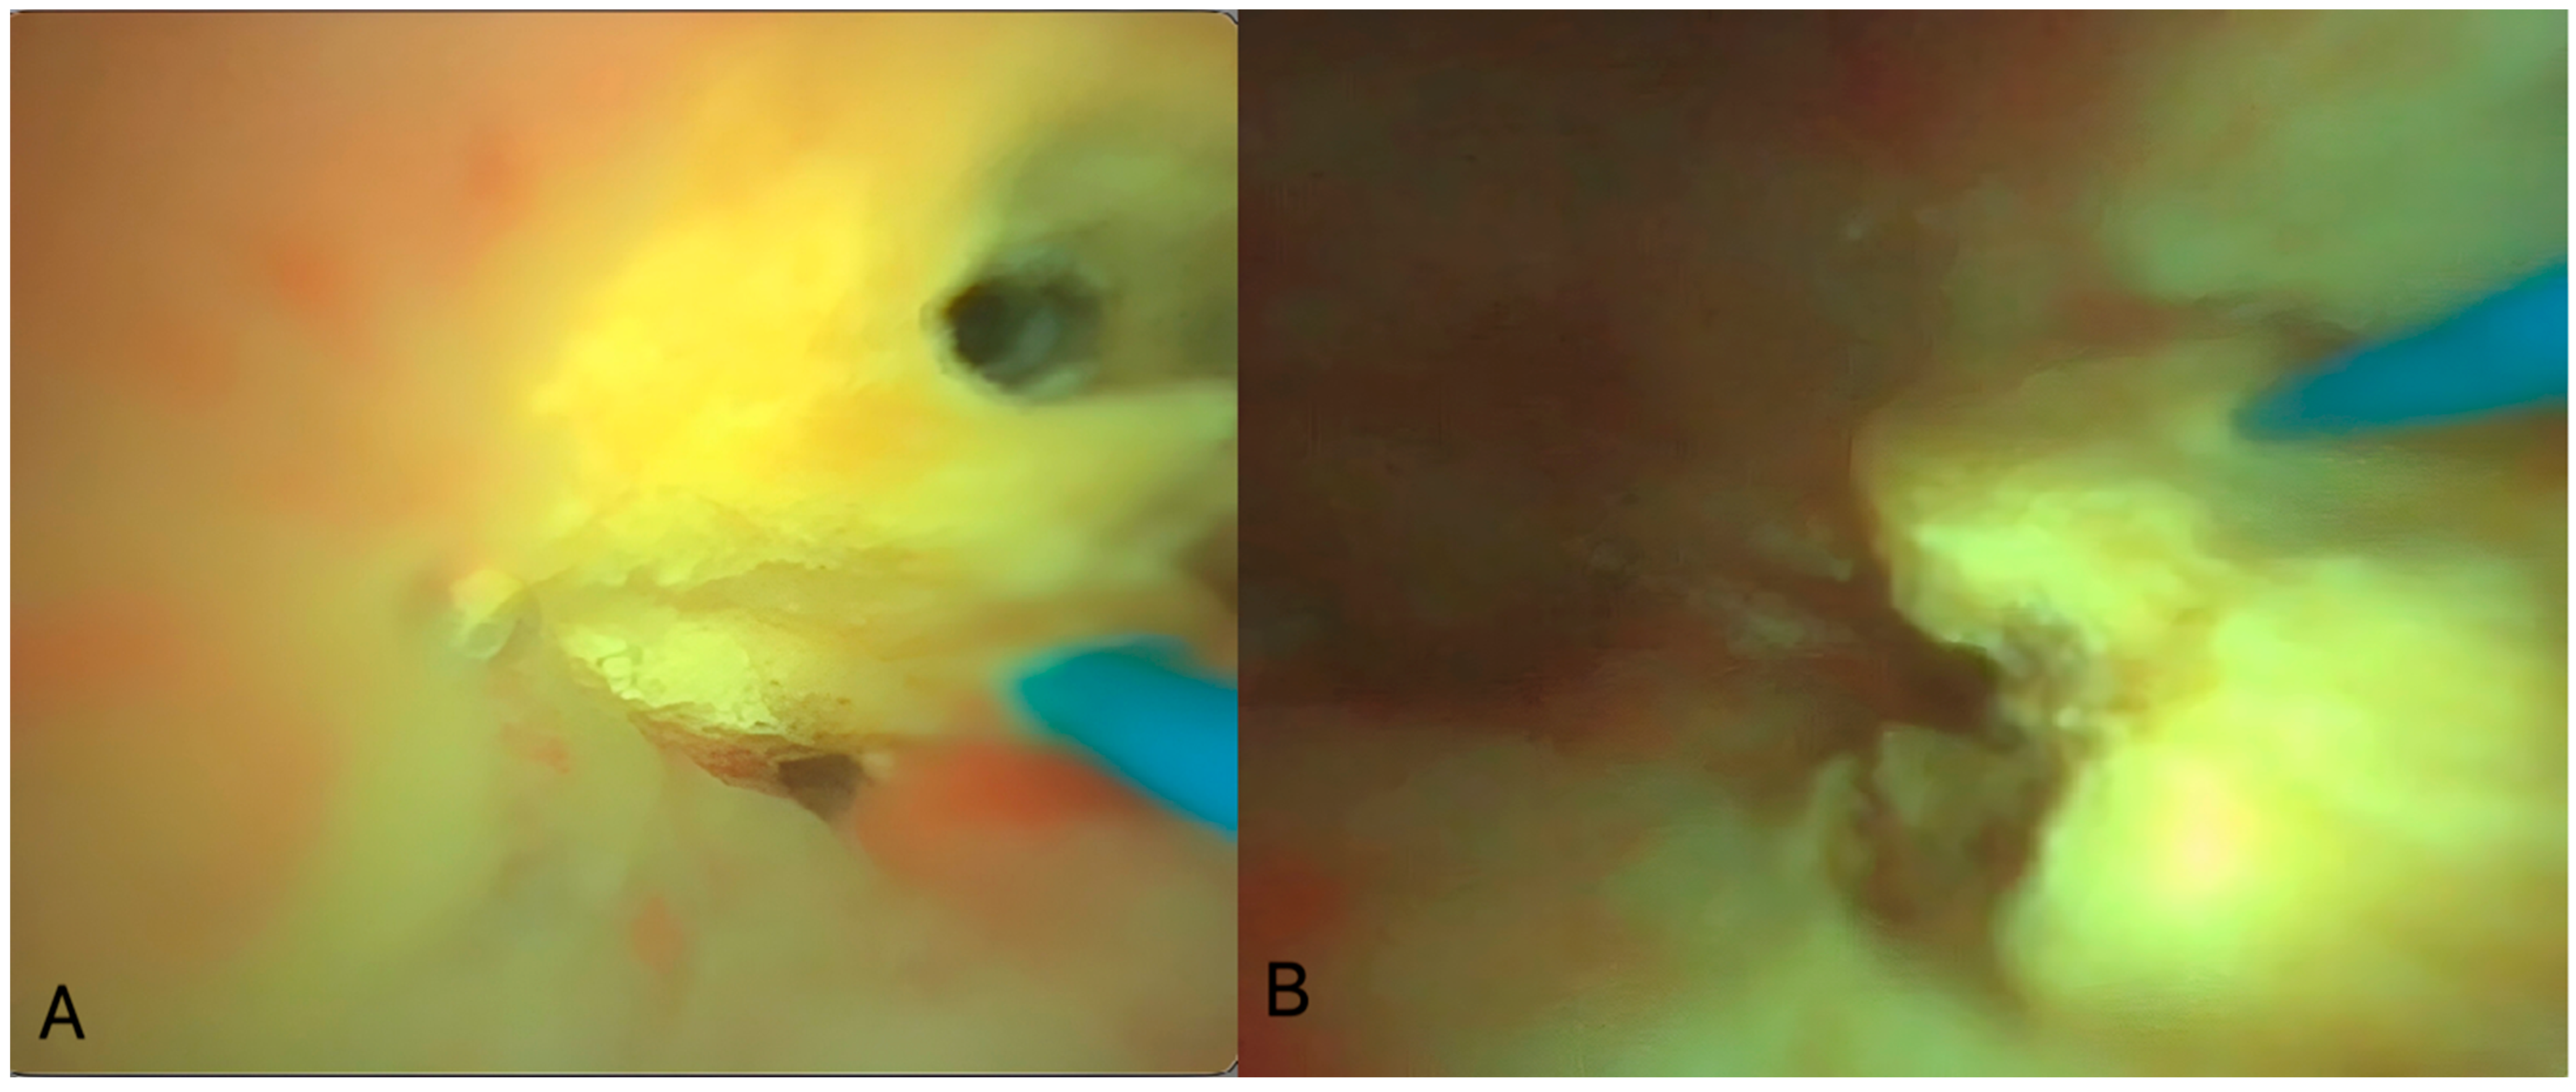

A non-contrast low-dose kidney–ureters–bladder (KUB) computed tomography (CT) was performed, reporting six stones in the right kidney of the patient with a cumulative stone burden of 3.2 cm2 (two stones per calyx without filling the pelvis). The largest stone was located in the upper calyceal system, measuring 10 × 14 mm and 810 Hounsfield units (HUs) (Figure 1 and Figure 2).

Figure 1. The preoperative CT scan of this case showing the stones in the right kidney. (A) Axial view of the upper pole stone, (B) coronal view of the upper pole stone, and (C) coronal view of the upper pole and middle pole stones. The stones are marked with red arrows.